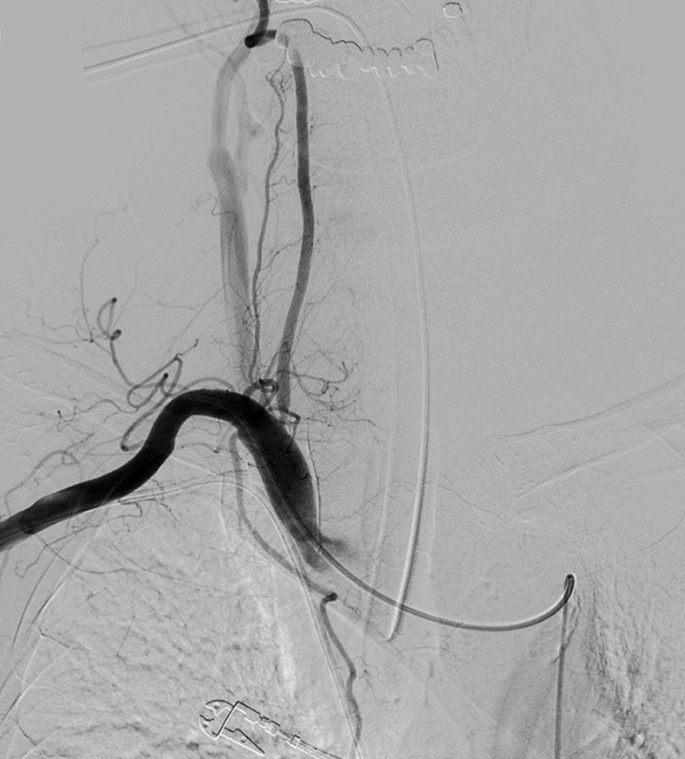

An 80 year-old man underwent ultrasound-guided FNA of the thyroid gland with a 23-gauge needle for the evaluation of a 1.8 × 2.2 cm well-defined, cystic nodule with internal tiny solid portion in the right lobe, which was identified by contrast-enhanced chest computed tomography (CT) taken one month before FNA (Fig. 1). Two passes were made into the lesion during the procedure. There were no complications during the procedure. Three hours later, the patient experienced swelling and progressive pain in the anterior neck. He was referred to the emergency room of our hospital with severe respiratory distress, four hours after the FNA. Emergency intubation was performed, and the patient remained hemodynamically stable. The patient was on a long-term anticoagulant medication prescribed for cardiovascular disease. Although the platelet count and liver functions were within normal range, the International Normalized Ratio (INR) was 1.35 (normal range: 0.085–1.15). An axial neck CT taken on emergency department revealed a large hematoma in the retropharyngeal space that caused anterior tracheal deviation (Fig. 2a). The sagittal neck CT showed extravasation of contrast media, suggesting active bleeding within the hematoma (Fig. 2b). Angiography was performed as a primary diagnostic and therapeutic procedure. Right subclavian angiography showed active bleeding arising from the right thyrocervical trunk in the neck, corresponding to the CT image (Fig. 3a). The right thyrocervical trunk was selected, and the culprit vessel was identified as the branch of the right inferior thyroid artery (ITA) (Fig. 3b). After superselection of the right ITA using microcatheter, embolization of the right ITA was performed using NBCA, and a post-embolization angiogram revealed successful hemostasis without active bleeding (Fig. 4). Although the retropharyngeal hematoma still remained, the patient’s respiratory rate was very stable under intubation state, and there was no evidence of increase in hematoma, which was confirmed on a daily follow up neck x-ray. Considering the risk of procedure-related complications, we decided to maintain conservative management for the hematoma. Six days after the embolization, when the patient was able to breathe around the endotracheal tube, it was removed without accident. Follow-up CT taken three weeks after TAE revealed a low-density lesion in the retropharyngeal space, indicating an old hematoma, which was smaller than it was before TAE without further treatment such as percutaneous drainage or open excision (Fig. 5). The patient recovered well and was discharged four weeks later. The hematoma in the retropharyngeal space was completely eliminated, which was confirmed by follow-up CT taken three month after the TAE, performed in an outpatient clinic. Unfortunately, we failed to obtain enough blood sample through the FNA, so failed to obtain the final pathological report. Additional FNA was not performed because the patient refused to take further work up for the thyroid nodule.